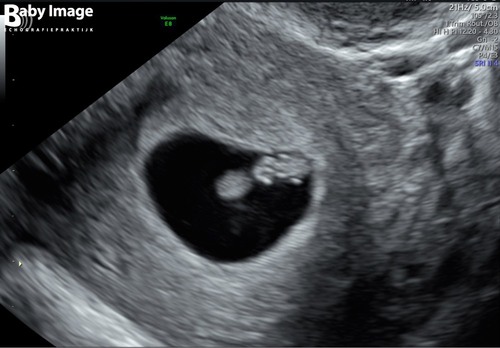

Ik zal de spits maar even afbijten, dit is ons kindje. Geschat door echo-me ...

Dit was ook maar een schatting van die mensen, is ook moeilijk omdat het nog zo klein is, maar op basis van de grootte dus 6+3. Betekent wel dat het sperma een paar dagen heeft overleefd!

Overigens was het hartje ook van buiten al goed te zien, maar toen ik erom vroeg wilde ze ook nog wel inwendige echo doen en daar zag je het nog beter. Ik heb ook hele mooie filmpjes maar dat kan niet hier :D

Wat is die van jou duidelijk zeg vergeleken met mij !! Qua 2 dagen verschil die van mij was nog inimini tegen de baarmoederwand aan